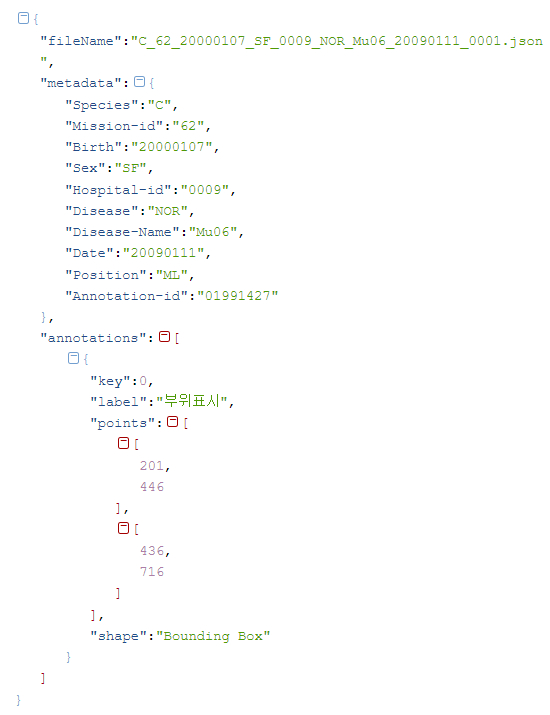

데이터 구성 항목 타입 필수 비고 유효값 / 허용범위 / 예시 유효값 설명 국문영 영문영 여부 Species 종별 string Y 종 (개 90%, 고양이 10% ) D, C 개(D), 고양이(C) 구분 Mission-id 과제 ID string Y 세부과제번호(복부, 흉부, 근골격계) 60, 61, 62 60 = 복부 61=흉부 62=근골격계 Birth 생년일 string Y 생년월일 ex) 20020829 형식 : YYYYMMDD Sex 성별 string Y 성별 (수컷, 암컷, 중성화수컷, 중성화암컷) IM, IF, CM, SF 형식 : Male(IM) / Female(IF) / Castrated male(CM) / Spayed female(SF) Hospital-id 병원 코드 string Y 원천데이터 제공병원코드 ex)0023, 0195 수집병원에 대해 일련번호를 정해 사용 (4자리) Disease 질환 유무 string Y 질환 유무 (정상 70%, 질환 30%) ABN, NOR 질환(ABN), 정상(NOR) Disease-Name 질환 부위-명 string Y 복부(Ab), 흉부(Ch), 근골격(Mu) 질환명분류:복부(10종),흉부(7종),근골격계(7종) Date 촬영 시간 string Y 촬영 시간/일자 ex) 20020829 Position 촬영 자세 string Y 촬영 자세 복부(60), 흉부(61) : VD, Lateral 근골격계(62):VD,Lateral,AP,ML Annotation-id 어노테이션 ID string Y 어노테이션 ID 11779877 어노테이션 포맷

어노테이션 포맷 구분 항목 타입 필수 설명 유효값 / 허용범위 / 예시 여부 shape 어노테이션 타입 string N 데이터가공시 선택박스 형태 (Bounding Box, Polygon(Segmentation)) Line, Polygon, Bounding Box points 좌표위치 array Y 폴리곤 혹은 바운딩 박스 좌표 구축데이터 파일명

- 종_질환부위_생년월일_성별_병원코드_질환여부_질환명_촬영시간_수집번호.json

- * 예시 : C_60_20160501_IF_0004_NOR_Ab02_20200822_0015.json